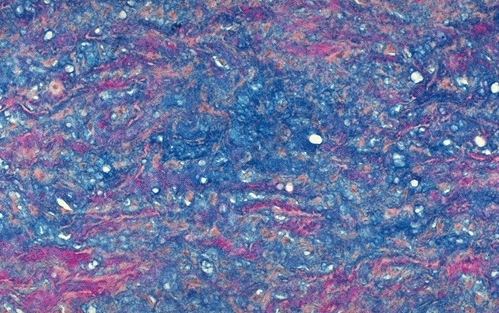

This is a mucin stain of the wall of the aorta. What do you see?

A

- Demonstrates cystic medial necrosis, typical for Marfan’s syndrome and causes the connective tissue weakness that explains the aortic dissection

- Pink elastic fibers, instead of running in parallel arrays, are disrupted by pools of blue mucinous ground substance